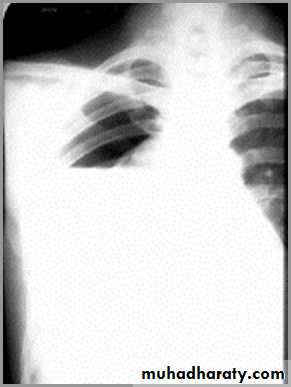

pneumothorax

When air enters the pleural space, the parietal and visceral pleura separate making the visceral pleura visibleThe thin white line of the visceral pleura is called the visceral pleural white line

You must see the visceral pleural white line to make diagnosis of pneumothorax!

Simple pneumothorax

In a simple pneumothorax, there is no shift of the heart or mediastinal structures (trachea)

Air in left hemithorax balances the air in the right hemithorax

Tension pneumothorax

Progressive loss of air into pleural space causing a shift of the heart and mediastinal structures away from side of pneumothoraxOpposite lung is compressed

Respiratory function severely compromised